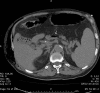

Fig. 3

Gangrene of the pelvis